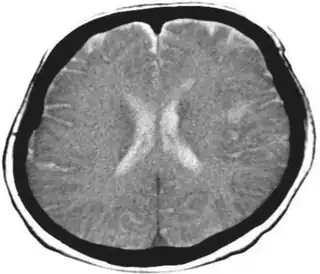

Diagnosis may be clinical if associated with dementia and other etiologies. In cases caused by stroke, MRI will show a corresponding stroke in the inferior parietal lobule. In the acute stage, this will be bright (restricted diffusion) on the DWI sequence and dark at the corresponding area on the ADC sequence.